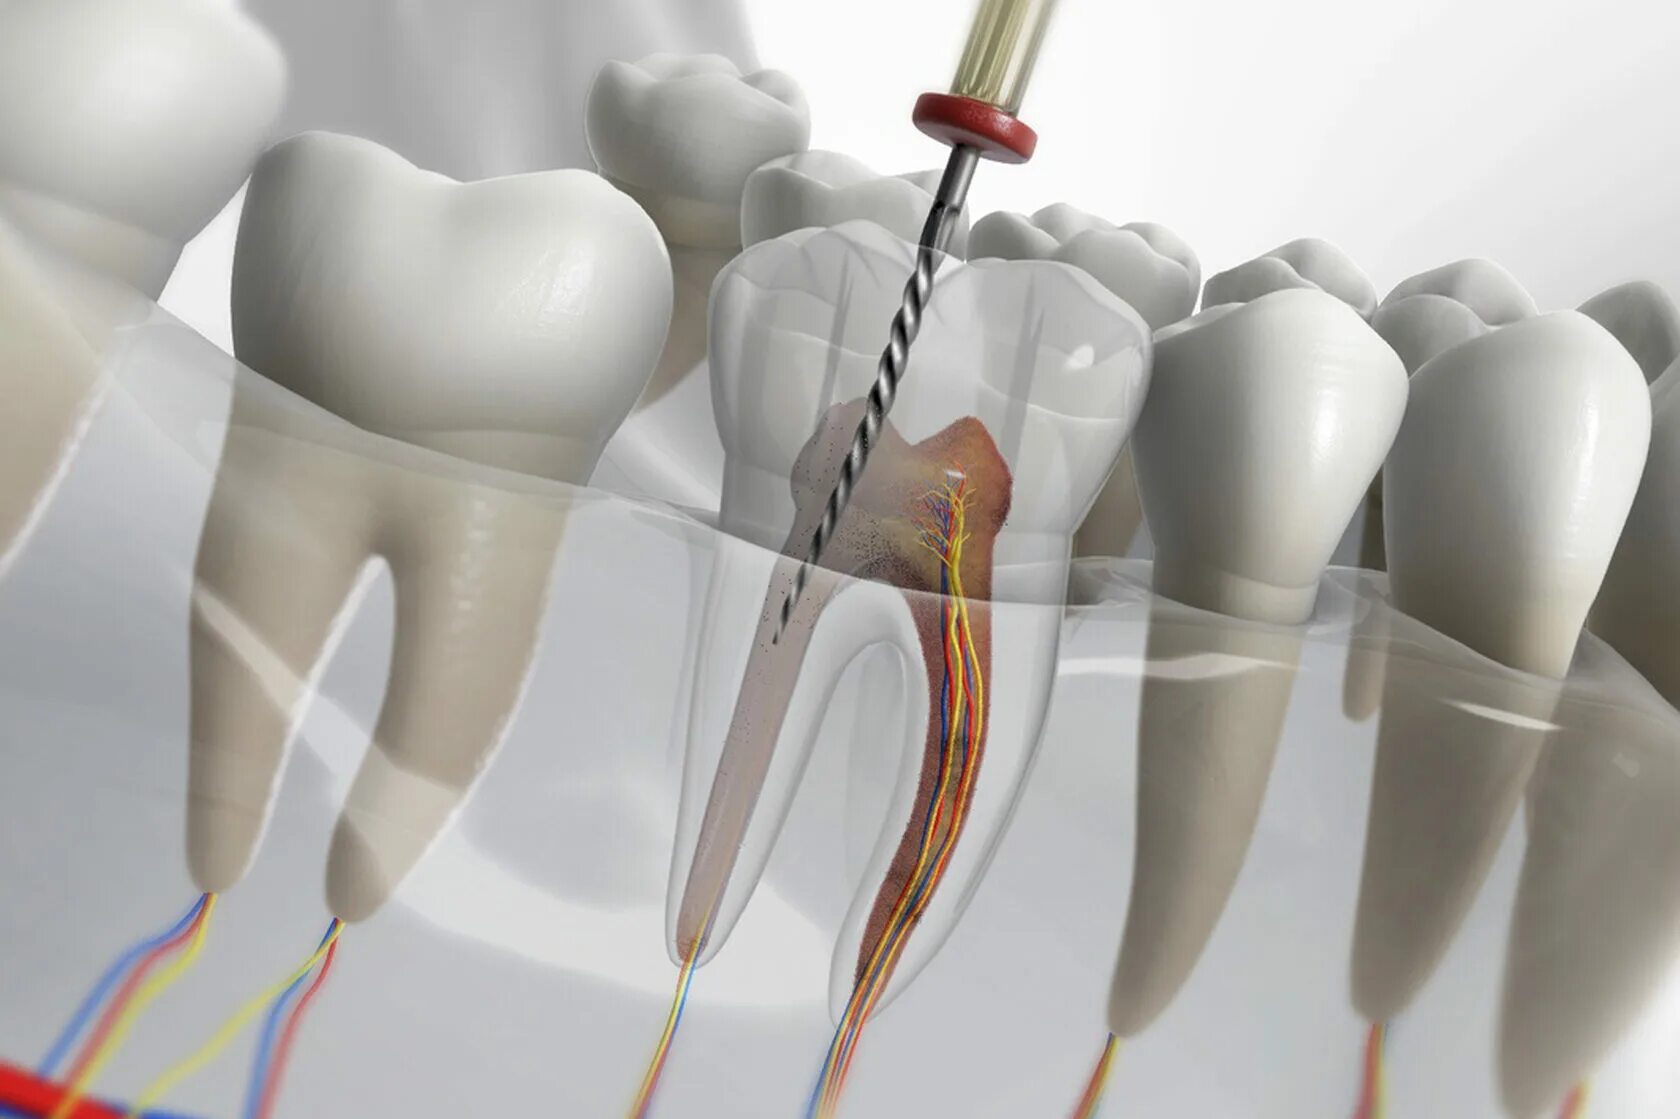

Удаление нервов в зубе и пломбирование